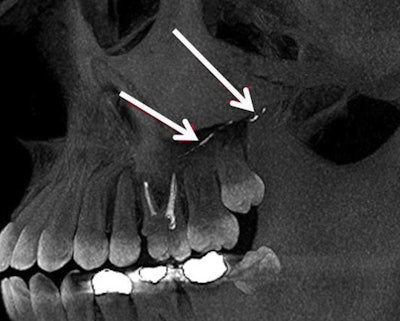

At the endodontic department, she underwent a clinical exam and imaging. A CBCT scan showed dislocation of opaque material from the canals of tooth #14 to the floor of the left maxillary sinus, posterior superior alveolar artery, infraorbital artery, and the area of the infraorbital foramen.